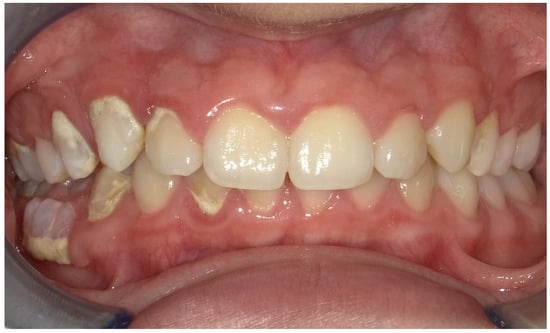

2.2. Clinical Findings

2.5. Follow-Up and Outcomes

3. Results